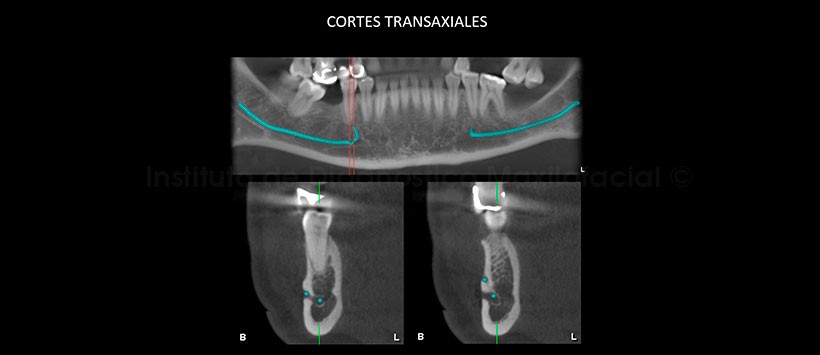

La tomografía computarizada de haz cónico, mediante los cortes transaxiales y tangenciales, muestra claramente la presencia de dos agujeros mentonianos en un mismo lado, en este caso en la parasínfisis mandibular del lado derecho; además, de su distribución a nivel de la tabla ósea bucal (Fig. 2 y 3).